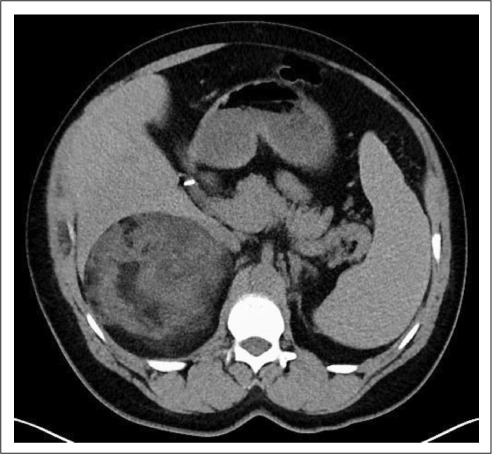

2018年的后续CT扫描显示右侧肾上腺肿物的最大尺寸为12.3 cm;同时也显示了明显更多的宏观脂肪(图4)。再次显示与SCD相关的脾脏和骨性改变。

图4